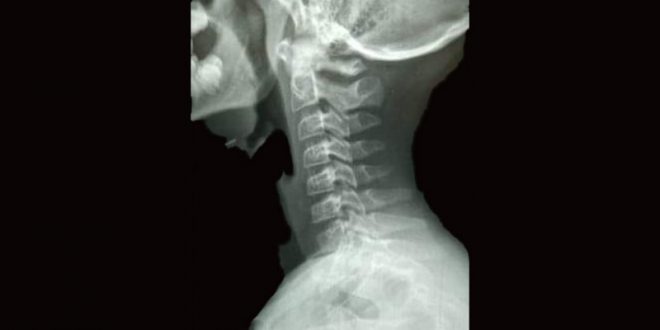

Una vez se tranquilizó, me comentó lo siguiente: qué estaba jugando con sus compañeros de clase y a la vez mojándose con unas botellas de plástico, pues era un convivió, a lo cual el profesor de nombre Marco Antonio Reveles Herrera va pasando cerca y por error lo mojaron, el cual se fue en contra de mi hijo, el cual lo tomó por el cuello y le restregó las botellas en la cara, no conforme, también los rasguñó.

Un profesor que estaba cerca, se acercó a auxiliar a mi hijo, lo cual enseguida lo llevaron a la dirección, lo cual mi hijo tiene lastimado el cuello y rasguños en la cara, lo cual tampoco puede pasar alimentos bien, por lo que hago responsable al profesor Marco Antonio Reveles Herrera de la secundaria Francisco Zarco número 7, ubicada en Tetela del Monte, Cuernavaca, Morelos, por la agresión física realizada a mi hijo. Yo esperé que se hiciera justicia, pero no han hecho nada, a lo cual pido de su ayuda para que se haga viral esto. Hoy fue uno de sus hijos de ustedes.